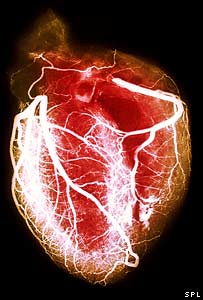

دل

دل کے مریضوں کی زیادہ اموات شرح کا تعلق ہسپتال میں داخلے کے وقت کم سسٹولک پریشر سے ہے۔